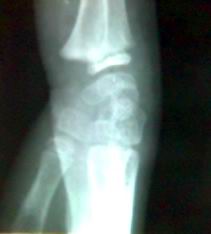

标题: X3837:腕关节外伤

骑自行车不慎摔倒,腕关节受伤

骺离骨折

桡骨远端骺离骨折.

典型

骨骺分离.骨密度低.半脱位.